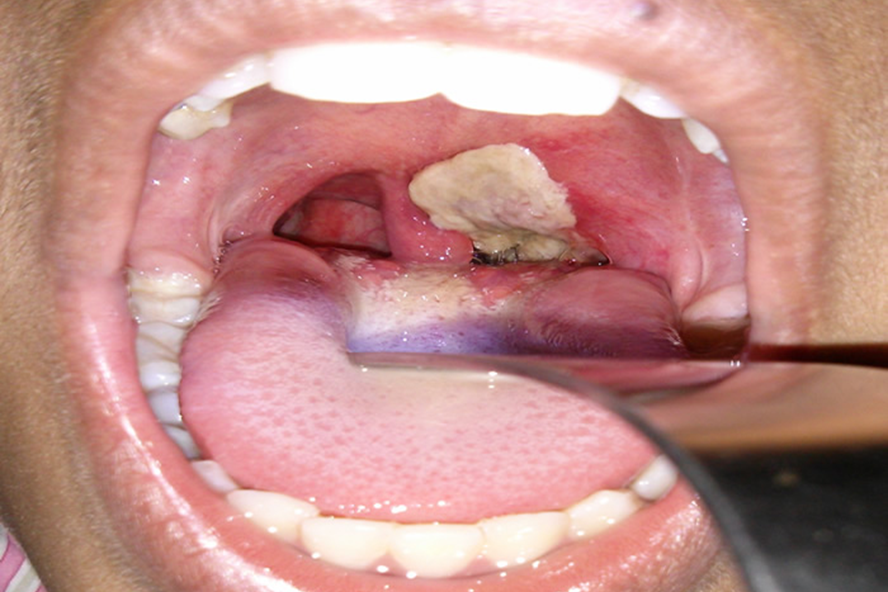

Triệu chứng dễ nhận thấy nhất của bệnh bạch hầu là hình thành mảng màu xám, dày ở họng và amidan. Ảnh: Internet.

Ông Nguyễn Văn Hùng, phó giám đốc Sở Y tế Đắk Lắk, cho biết bạch hầu là bệnh nguy hiểm, nguy cơ tử vong cao và lây lan rất nhanh. Triệu chứng dễ nhận thấy nhất của bệnh bạch hầu là hình thành mảng màu xám, dày ở họng và amidan.